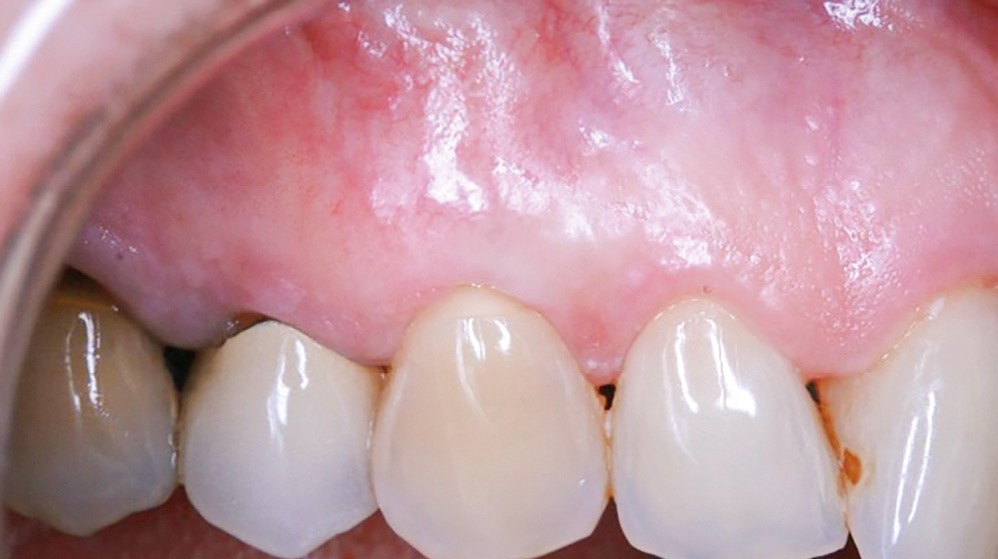

De nombreuses techniques de lambeaux déplacés latéralement, lambeaux déplacés coronairement (fig. 4), enveloppes ou tunnels (fig. 5) ont fait l’objet de publications et présentent des résultats quasi identiques en termes de recouvrement. Leurs points communs sont un recouvrement complet du greffon, une dissection en épaisseur partielle suffisante pour assurer un positionnement du lambeau sans tension et l’absence (quand cela est possible) d’incision de décharge. Le choix d’une ou l’autre technique dépend surtout de l’expérience du praticien et de la quantité de tissu disponible apicalement ou latéralement.